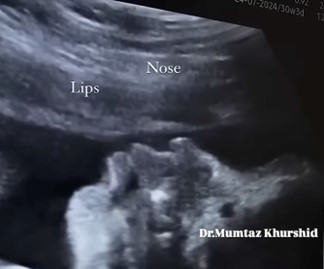

Η διαδικασία της κατάποσης είναι σημαντική για τη θρέψη και την ενυδάτωση του ανθρώπου και παίζει πρωταρχικό ρόλο στη διατήρηση τόσο της καλής μας υγείας όσο και της ποιότητας ζωής μας. Ο μηχανισμός της κατάποσης εμφανίζεται στην εμβρυϊκή ηλικία των τριών μηνών, επιτρέποντας στο έμβρυο να καταπίνει αντανακλαστικά το αμνιακό υγρό (βλ. παρακάτω εικόνες).